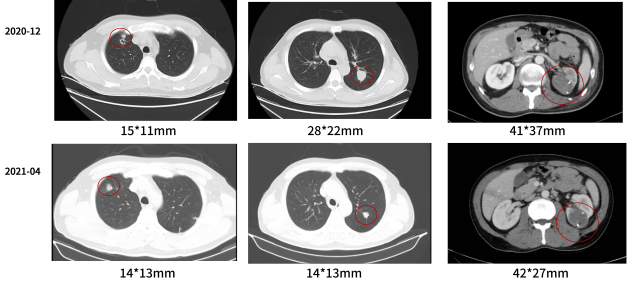

2020-12 - 2021-09

一线:帕博丽珠单抗 + 阿昔替尼

治疗结局:复查评效 SD(缩小)

病情变化

临床诊断

左肾透明细胞癌伴肉瘤样分化 TxN0M1 IV 期

双肺转移

后腹膜转移